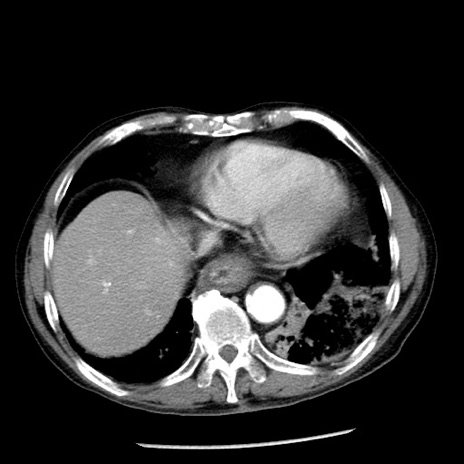

症例26(横断像)

【症例】80歳代男性

【主訴】嘔吐

【現病歴】昨晩2回嘔吐あり、今朝になっても嘔吐あり。来院。

【既往歴】胃潰瘍

【身体所見】意識清明、BT 37.6℃、BP 166/95mmHg、HR 100bpm、SpO2 97%、腹部:平坦・軟、腸蠕動音聴取良好、圧痛なし。

【データ】WBC 21900、CRP 1.46